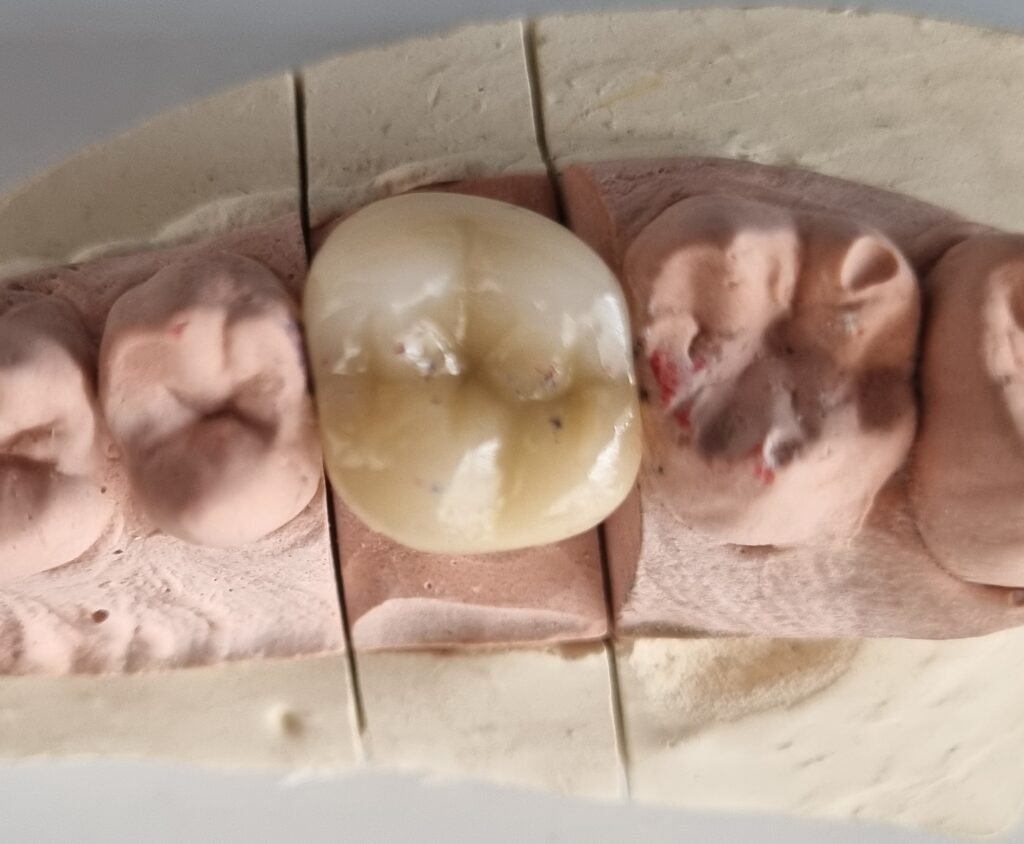

Resinas e incrustaciones

La caries dental es la enfermedad bucal número uno que aqueja a la población mundial. Así que probablemente presentes caries en algunos dientes y no lo sepas. Nosotros te hacemos tu revisión, diagnóstico y plan de tratamiento para la eliminación de caries; así como la colocación de resinas o incrustaciones, según sea el caso.